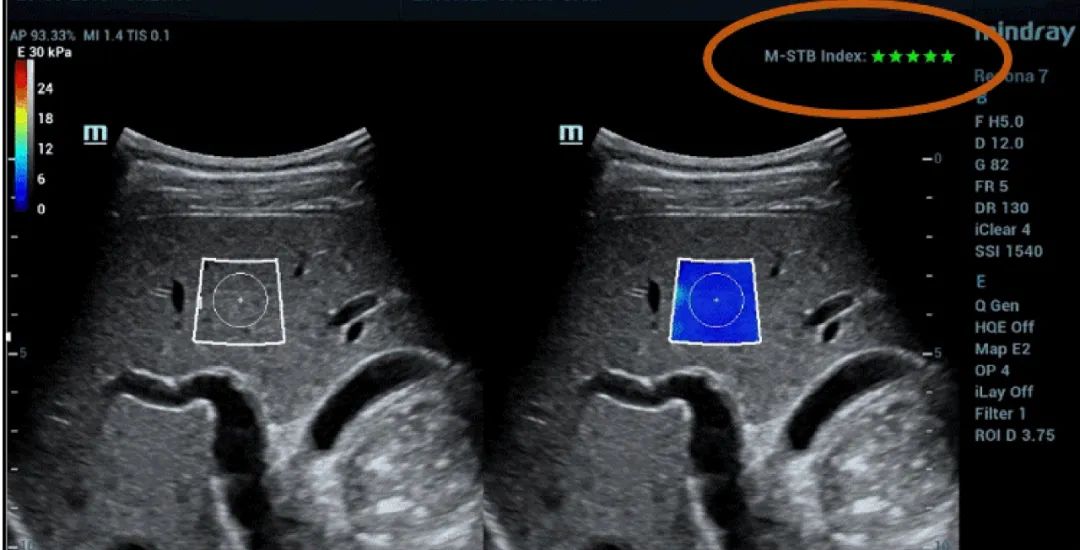

Рисунок 1 (продолжение): (e) Изображения, полученные с помощью 2D SWE (STE; Mindray, Шэньчжэнь, Китай). Приводятся два критерия качества: индекс стабильности (M-STB), отображаемый звездочками (наибольшая стабильность- пять звездочек зеленого цвета), и карта надежности (RLB), с цветами от фиолетового до зеленого - последний означает высокую надежность. Звездочки являются индикатором движения во время получения данных. Если количество отображаемых звездочек менее четырех, значит, во время получения данных наблюдается значительное движение, и этот кадр не следует использовать для измерения жесткости ткани печени. (f) Полученные изображения

Таким образом, технология Sound Touch Elastography (STE) компании Mindray обеспечивает высокую надежность результатов измерений, получаемых во время исследования с помощью 2D-эластографии сдвиговой волной, благодаря коэффициентам качества и достоверности, включая индекс стабильности (M-STB), карту надежности (RLB), индекс надежности (RLB), и т. д.

Индекс M-STB указывает на наличие/степень помех, вызванных дыханием пациента или движениями оператора. Индикатор представлен в виде звездочек (наибольшая стабильность- пять звездочек зеленого цвета), надежное изображение должно иметь ≧4 зеленых звездочки.